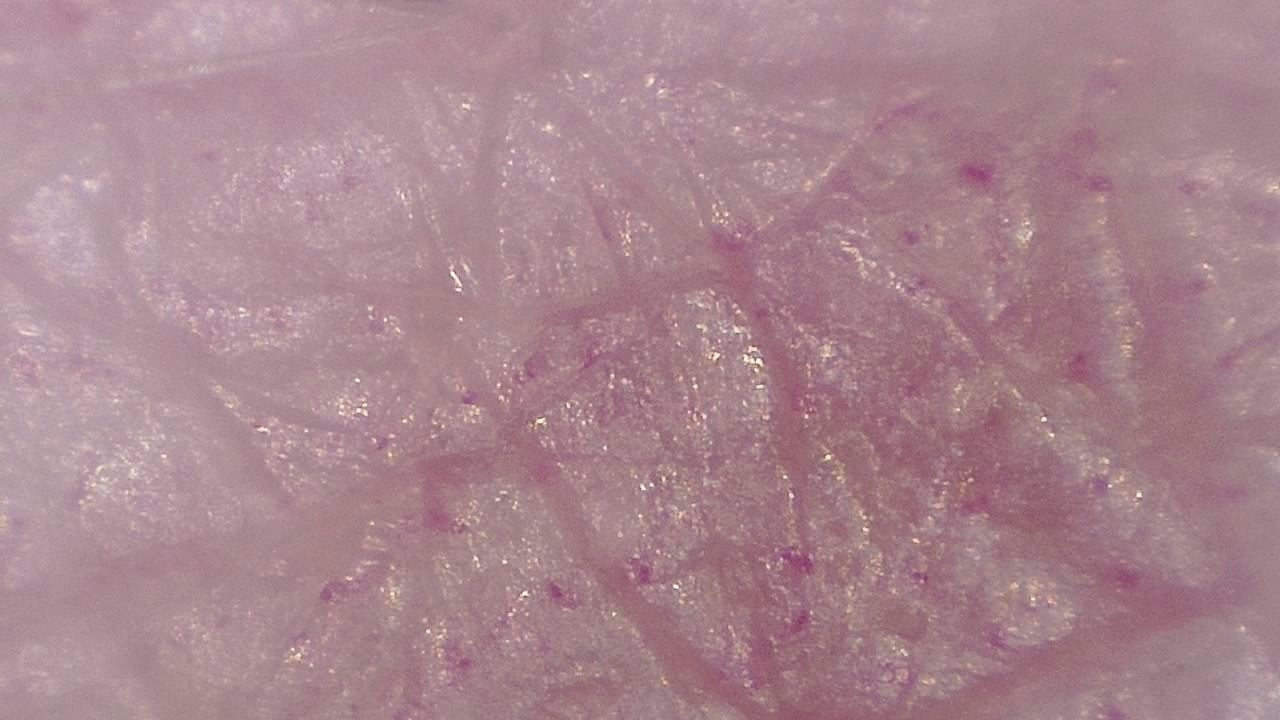

With variable magnification, it is possible to examine everything from superficial structures to deeper epidermal layers, identifying pigmentation patterns, abnormal vascularization, and textural changes that may go unnoticed to the naked eye.

- Visualization of dermal structures with up to 250× magnification

Image gallery

Click any image to enlarge